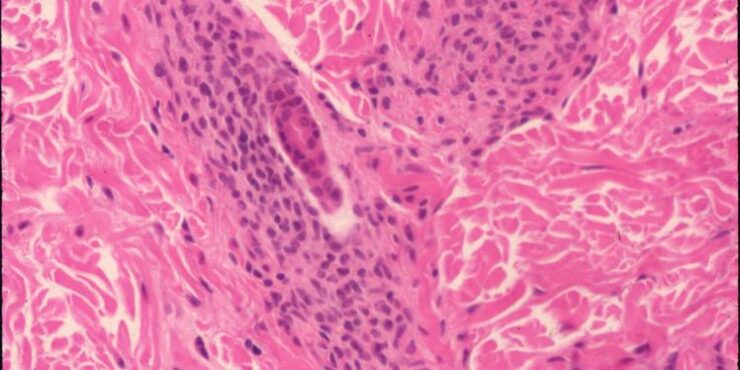

Read MoreCylindroma =الأسطوانوم OLYMPUS DIGITAL CAMERA OLYMPUS DIGITAL CAMERA OLYMPUS DIGITAL CAMERA OLYMPUS DIGITAL CAMERA